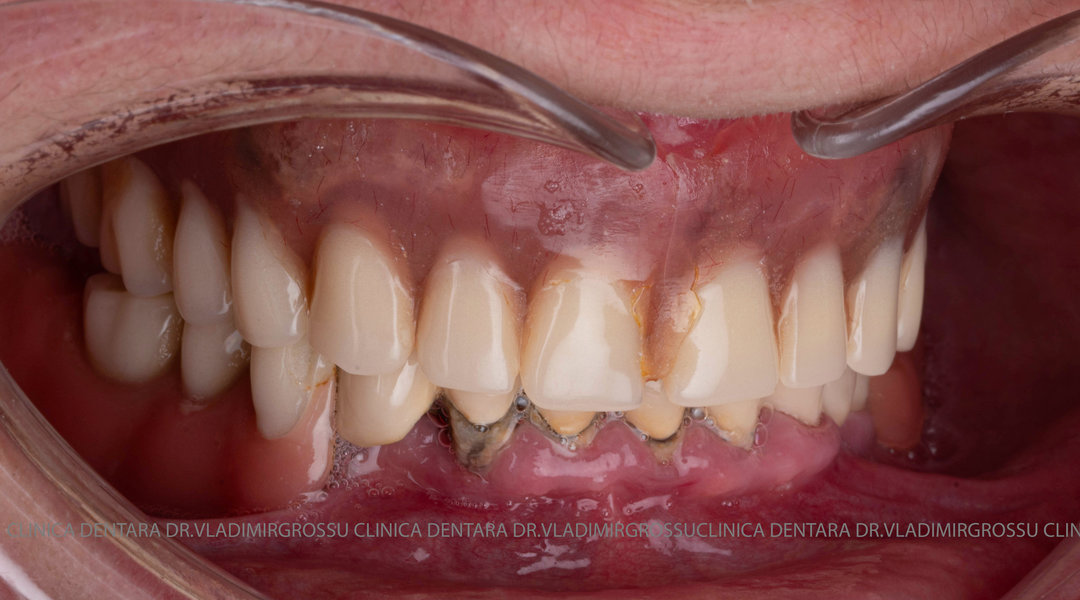

Tomografii (CBCT)

Caz 1